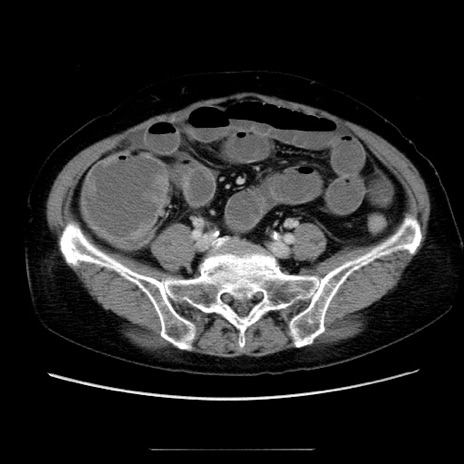

冠状断像

【症例】70歳代女性

【主訴】お腹が張る

【現病歴】1週間くらい前から腹部膨満の自覚あり。昨日夜から増悪したため、本日救急外来受診。

【身体所見】意識清明、BT 36.5℃、BP 165/106mmHg、HR 80bpm、SpO2 98%、腹部:膨満、軟、自発痛・圧痛なし、触診にて不快感あり、腸蠕動音:減弱

【データ】WBC 12600、CRP 1.04